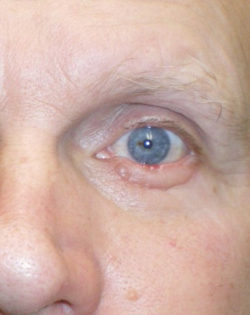

- Before/After